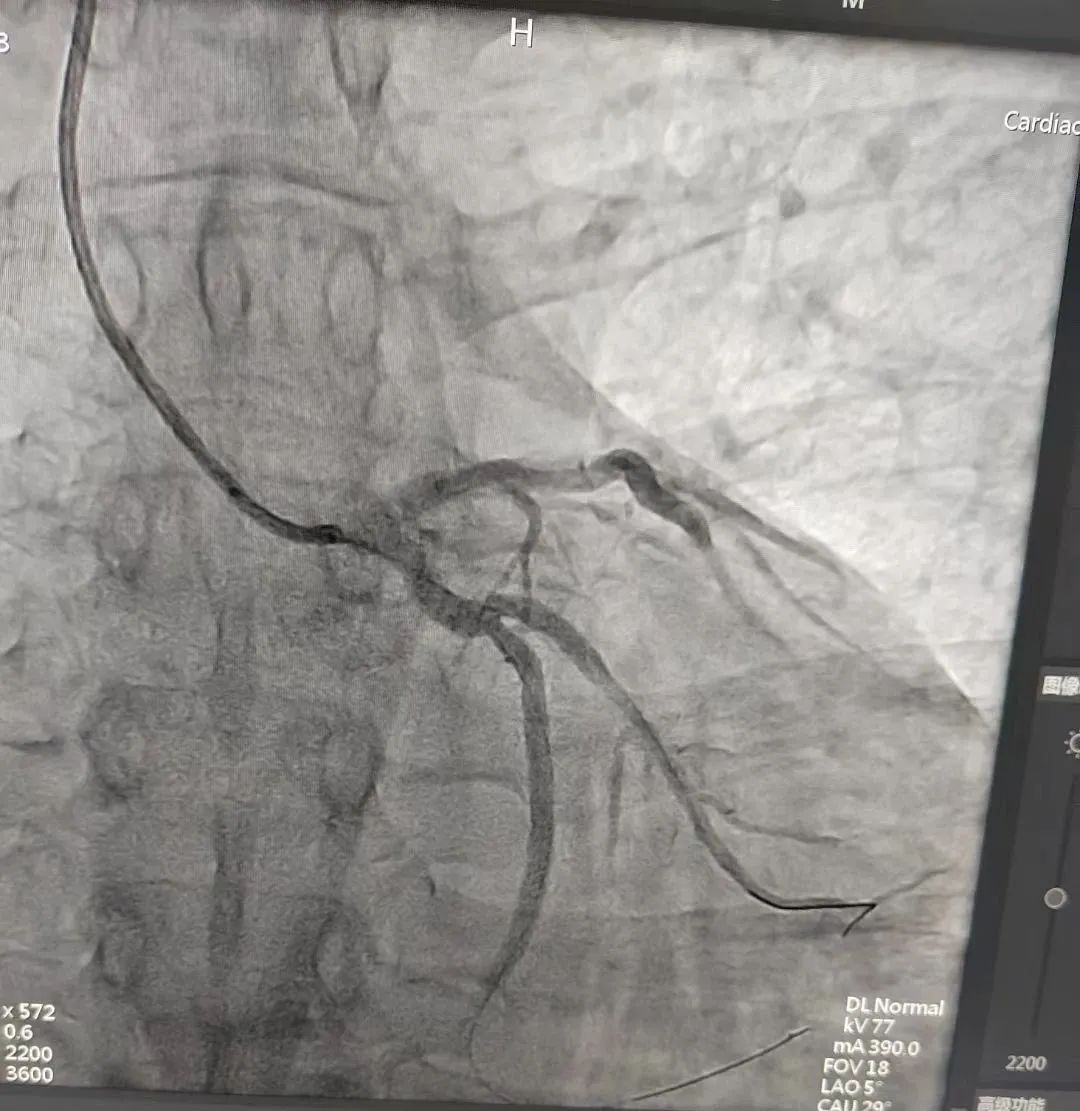

图为血管开通后重复造影结果。